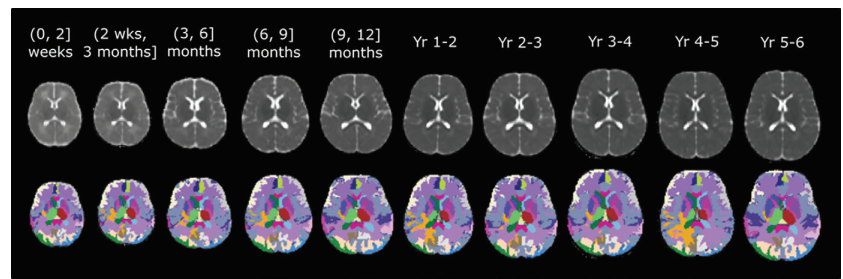

年龄相关的三维(3D)表观扩散系数(ADC)图谱 。 上图:特定年龄的3D ADC图谱 。 下图:感兴趣区域分割结果 。 不同的颜色表示不同的区域 。